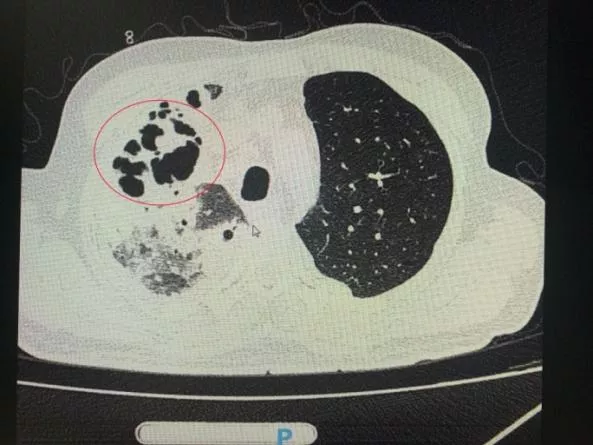

番禺院区呼吸内科何梦璋主任接诊后,对钟叔进行详细检查。此时,钟叔的病情已经十分危急,由于不能自主呼吸,他带上了无创呼吸机辅助呼吸治疗。看到钟叔胸片时,医护人员头皮也一阵发麻,胸部CT可见双肺多发的炎症浸润、双肺多发空洞。通俗来说,钟叔的肺部已经被病原体蚕食,啃出无数个大小各异的洞!可怕的是,这种病变对肺功能的破坏是永久性、不可恢复的。根据钟叔病史以及胸部CT结果,最终诊断为“吸入性肺脓肿”。

钟叔的肺部被病原体蚕食,啃出无数个大小各异的洞。